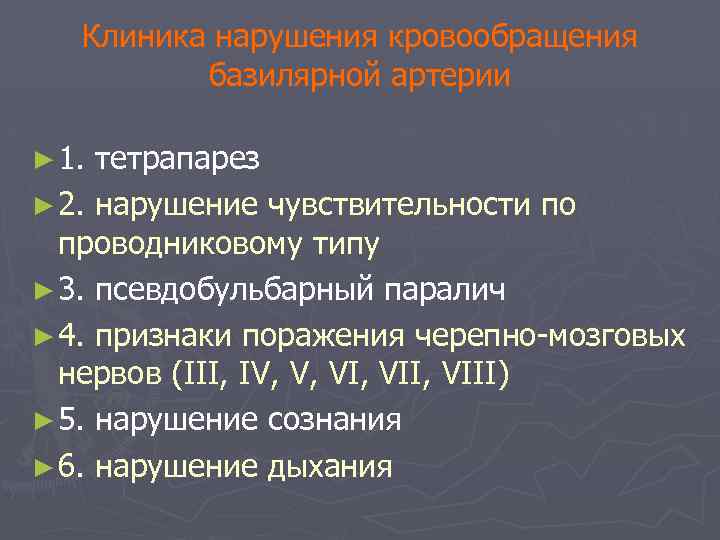

Клиника нарушения кровообращения базилярной артерии ► 1. тетрапарез ► 2. нарушение чувствительности по проводниковому типу ► 3. псевдобульбарный паралич ► 4. признаки поражения черепно-мозговых нервов (III, IV, V, VII, VIII) ► 5. нарушение сознания ► 6. нарушение дыхания